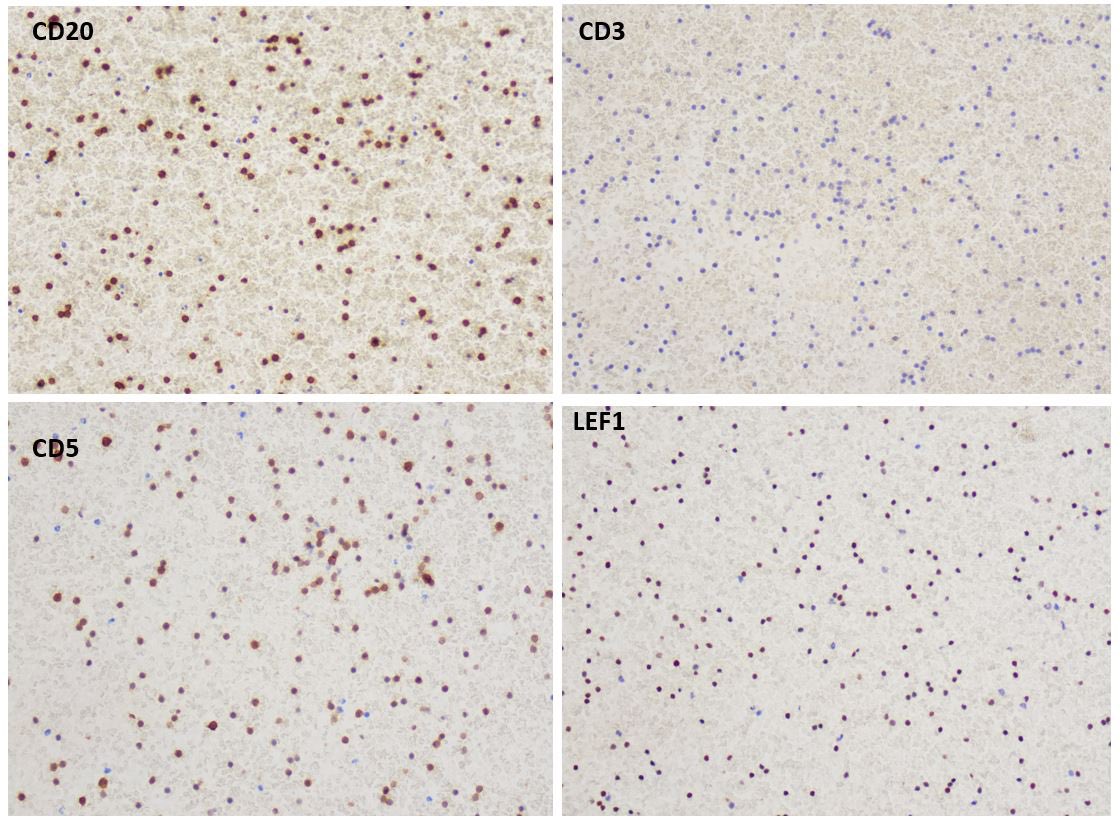

Pre-auricular nodule x 1month from 31yo patient, no other complaint. #pathtwitter #surgpath #ENTpath #hemepath #pathboards Einstein Montefiore Pathology Ridin Balakrishnan, MD Hansini Laharwani Siba El Hussein, MD Mitul B. Modi, MD Tristan Rutland MBBS FRCPA IFCAP Jerad Gardner, MD Kamran Mirza MD PhD - کامران مرزا

63/male with abdominal lymphadenopathy. DQ gave the initial clue to hemepath diagnosis. Positive CD3/5/7/25. CD30 diffuse, ALK1/CD20 negative. CD30+ Mature T-cell lymphoma. D/D ALCL or ATLL HTLV1 is positive! #cyto #hemepath #PathTwitter Kevin Kuan Yanhua Wang #bridgingcytoheme